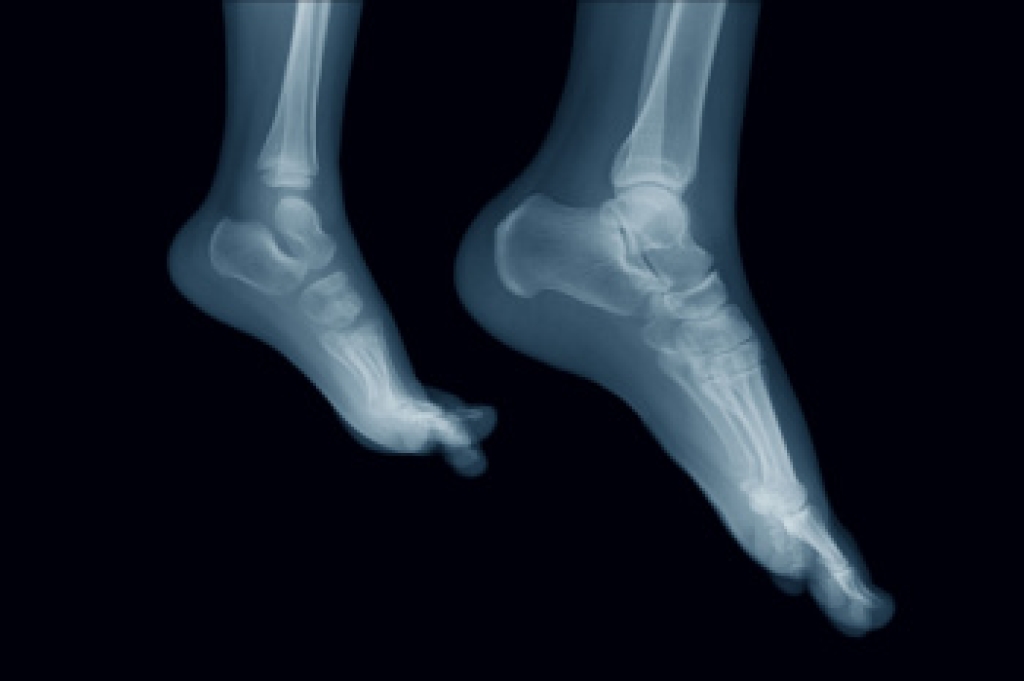

In many cases the cause of toe pain is obvious, but in others, a podiatrist may want to use more advanced methods to determine the problem. These can range from simple visual inspections and sensation tests to X-rays and MRI scans. Prior medical history, family medical history, and any recent physical traumatic events will all be taken into consideration for a proper diagnosis.